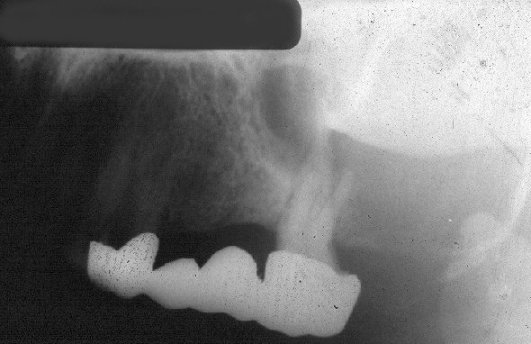

- Ακτινογραφικά στα αρχικά στάδια η αλλοίωση είναι μονόχωρη ακτινοδιαύγαση ενώ σε μεταγενέστερα στάδια εμφανίζονται εντός της διαύγασης οστικά διαφράγματα που μετατρέπουν την αλλοίωση σε πολύχωρη.

- Συνηθισμένο εύρημα είναι η απορρόφηση των ριζών των παρακειμένων δοντιών.